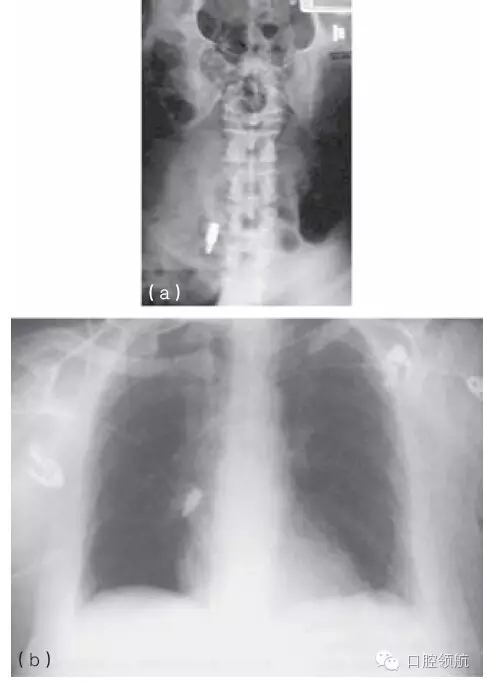

一旦器械或是其他異物,如種植體部件不慎誤吞,應(yīng)立即讓患者拍攝胸片進(jìn)行評(píng)估(圖10.42a,b)。應(yīng)咨詢專家是否應(yīng)將異物取出,或是通過胃腸道排出。

圖10.42 (a,b)X線片顯示被誤吞的螺絲刀。